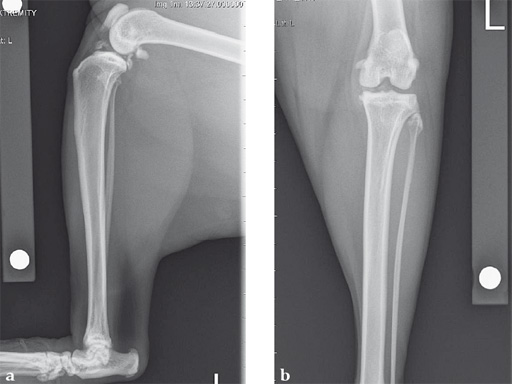

A 10-year-old female, spayed, 6.0 kg cat had a partial tear of the left cranial cruciate ligament, meniscal mineralization, and a medial meniscal tear. The cat was treated with a partial meniscectomy and TPLO . A 2.0 mm TPLO plate was perfect for this cat due to the slope of the tibial plateau (25) and the size of the cat. Three 2.0 mm locking screws were used proximally and three 2.0 mm cortex screws were used distally. The contour of this plate does not perfectly match the contour of the proximal tibia, but use of locking screws in this segment avoids any potential angulation of the segments as the screws are tightened. The cat healed uneventfully and returned to normal function.